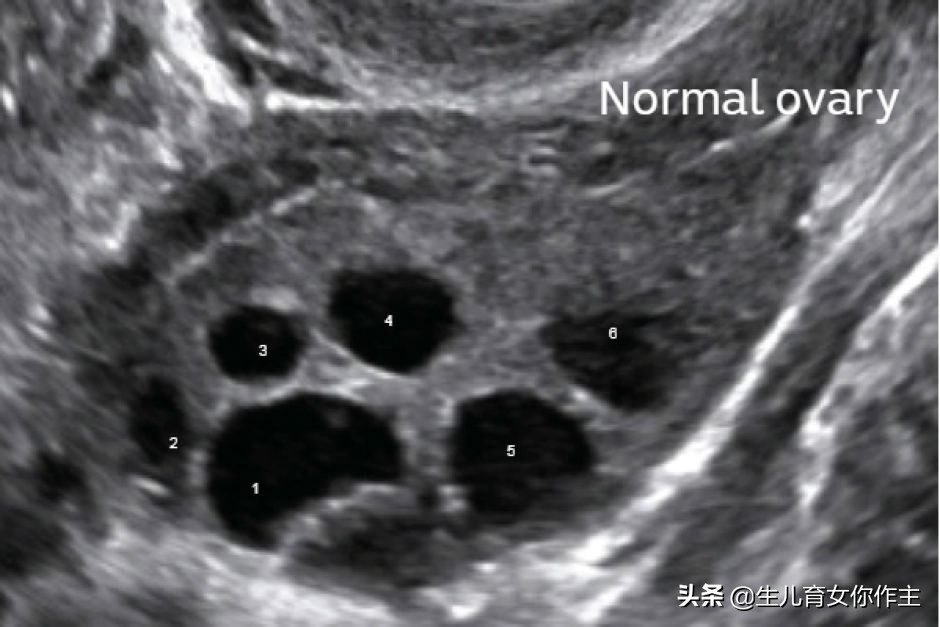

超声法——1号是优势卵泡(图片来自网络)

超声检查法

经阴道超声检查可以准确地确定排卵时间,被认为是检测排卵的标准参考检查。

利用B超观察卵泡大小及变化,来判断排卵时机,是最直观的一种方法。但这种方法需要多次往返医院,而且费用较高,应用并不多,一般仅用于人工生殖。